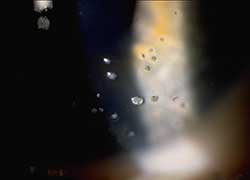

"name": "Vascularized Limbal Keratitis (VLK)",

"detail": "<h2>Symptoms</h2>\n\n<ul>\n\t<li>Patient may notice red area at limbus</li>\n\t<li>Slight stinging or irritation may be reported</li>\n</ul>\n\n<h2>Signs</h2>\n\n<ul>\n\t<li>Superficial vascularized lesion of the corneal periphery at the 3 and/or 9 o&rsquo;clock locations</li>\n\t<li>Wing shaped, raised lesion encroaching the cornea from the bulbar conjunctiva</li>\n</ul>\n\n<h2>Etiology</h2>\n\n<ul>\n\t<li>Sequellae to chronic inflammation in GP wearers</li>\n\t<li>Inadequate tear film and wetting result in punctate epithelial keratopathy</li>\n</ul>\n\n<h2>Prevalence</h2>\n\n<ul>\n\t<li>Rare</li>\n</ul>\n\n<h2>Differential Diagnosis</h2>\n\n<ul>\n\t<li>Pterygium (degenerative and hyperplastic condition in which the conjunctiva actively invades the cornea)</li>\n\t<li>See: <a href=\"/condition/63\">Hyperemia and Vascularization &ndash; Differential Diagnosis</a></li>\n</ul>\n\n<h2>Management</h2>\n\n<ul>\n\t<li>Eliminate 3 and 9 o&#39;clock staining through modification of the GP design</li>\n\t<li>Change to soft lenses, daily disposable or SiHy</li>\n\t<li>Use rewetting drops or reduce wearing time</li>\n</ul>",